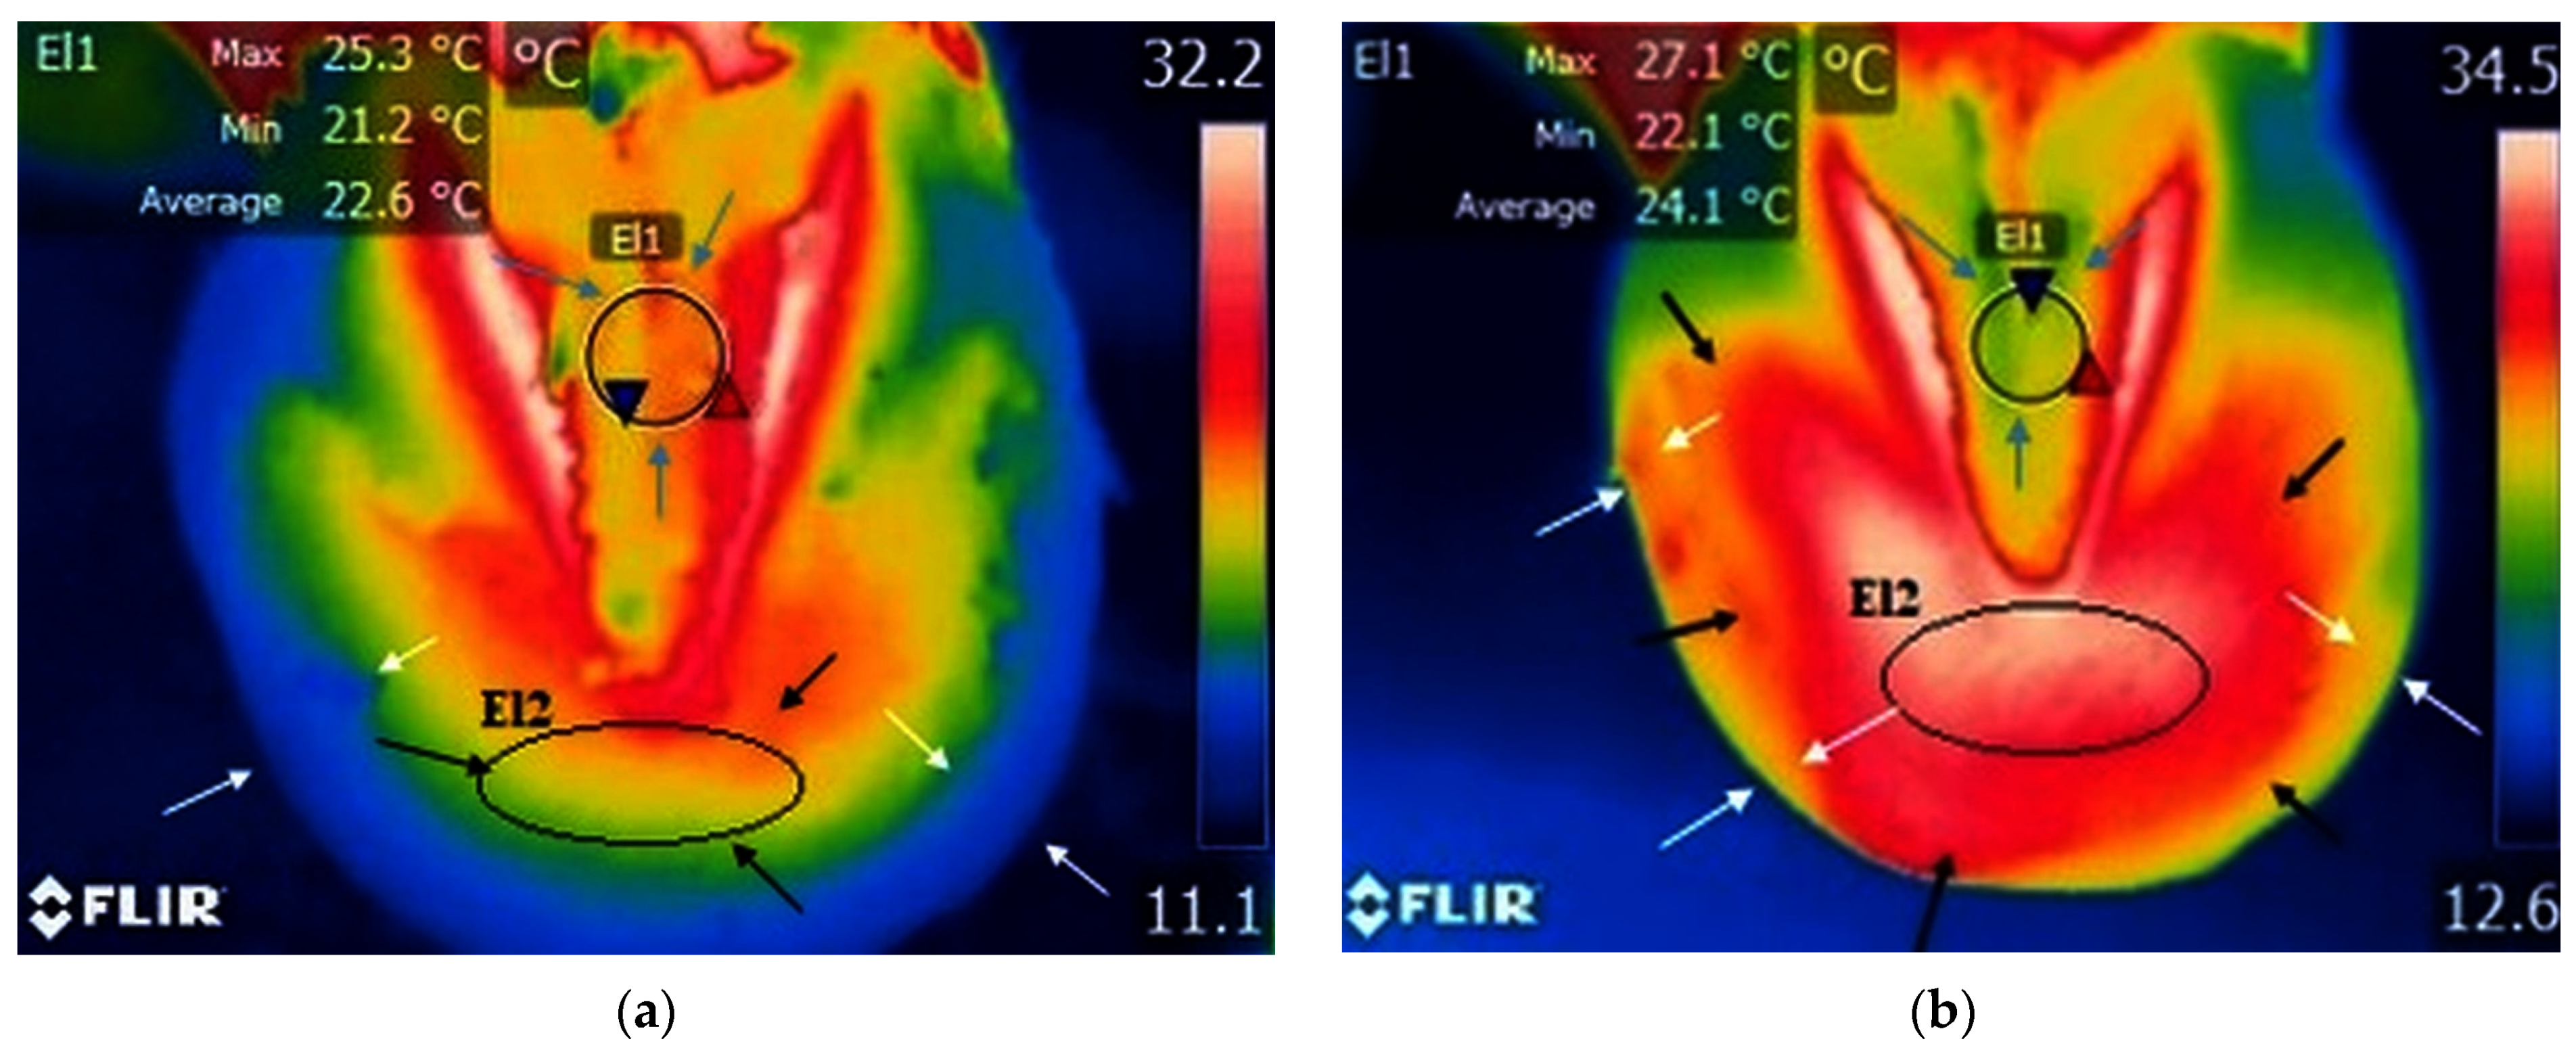

A small area of increased temperature was noticed between the frog and the hoof wall, which corresponds to the toe area, in the study group with palmar foot pain (Figure 3a and Table 1). The m.m.v.t. of the toe area was 20.6 °C.

Figure 3.

Study group, limbs with palmar foot pain: (a) sole surface before training—small surface of increased temperature in the frog area (blue arrows) and toe area (black arrows); reduced temperature along the hoof wall (white arrows); minimum temperature recorded in the area—blue triangle spot; maximum temperature recorded in the area—red triangle spot; (b) sole surface after training—increased temperature and wider surface of increased temperature in the toe area (black arrows); no obvious changes in local temperature in the frog area (blue arrows); increased temperature along the hoof wall (white arrows); minimum temperature recorded in the area—blue triangle spot; maximum temperature recorded in the area—red triangle spot.

A small area of increased temperature was present near the toe in the study group with the contralateral non-lame limb (Figure 4a and Table 1). The m.m.v.t. value of the toe area was 27.7 °C.

Figure 4.

Study group, non-lame limbs: (a) sole surface before training—reduced temperature and small surface of temperature in the frog area (blue arrows); increased area of temperature on hoof wall surface (white arrows); reduced temperature in the toe area (black arrows); (b) sole surface after training—increased temperature and wider surface of increased temperature in the frog area (black arrows); increased surface of temperature along the hoof wall (white arrows); small surface of reduced temperature in toe area (blue arrows); minimum temperature recorded in the area—blue triangle spot; maximum temperature recorded in the area—red triangle spot.

In the case of the control group, the toe area presented limited temperature increases (Figure 5a and Table 1). The m.m.v.t. for toe area was 24.0 °C.

Figure 5.

Control group: (a) small surface of increased temperature in the toe area (black arrows); small surface of increased temperature in the frog area (blue arrows); reduced temperature of the hoof wall (white arrows); minimum temperature recorded in the area—blue triangle spot; maximum temperature recorded in the area—red triangle spot; (b) increased local temperature and wider surface of increased temperature in the toe area (black arrows); increased local temperature and wider surface of increased temperature in the frog area (blue arrows); increased temperature along the hoof wall (white arrows); minimum temperature recorded in the area—blue triangle spot; maximum temperature recorded in the area—red triangle spot.

In horses with palmar foot pain, the surrounding temperature was not raised in the frog area (Figure 3a and Table 1), and the m.m.v.t. in the frog area was 21.1 °C.

A larger area of increased temperature was found in the toe region in horses with palmar foot pain (Figure 3b, Table 1 and Table S1). The m.m.v.t. for the toe area was 27.7 °C.

In the study group with the contralateral non-lame limb, the local temperature of the toe area remained the same (Figure 4a, Table 1 and Table S2). The m.m.v.t. for toe area was 28.8 °C.

In the control group the temperature rates in the toe area remained unchanged (Figure 5a, Table 1 and Table S3), with m.m.v.t. of 26 °C.

The m.m.v.t. for the toe area reflected an obvious increase in temperature following training sessions, with values of up to 7.1 °C in the case of the palmar foot pain group, respectively, and lower rates for the non-lame limb group, with temperatures increased by only 1.1 °C. Similar to the latter, the temperature increased by only 2 °C in the case of the control group.

In the study group with palmar foot pain, a smaller area of lowered temperature was found in the frog area (Figure 3b, Table 1 and Table S4), with m.m.v.t of the frog at 22.2 °C.

In the study group with the contralateral non-lame limb, the area of increased temperature widened in the frog area (Figure 4b, Table 1 and Table S5), with the m.m.v.t. being 28.7 °C.

In the control group, the frog area presented a wider area of increased temperature rates (Figure 5b, Table 1 and Table S6), with the m.m.v.t. of the frog area at 25.2 °C.

The m.m.v.t. was low in the frog area for horses from the study group with palmar foot pain compared to values obtained for the horses from the contralateral non-lame limb and control groups, both before and after training sessions. The m.m.v.t. after training in horses with palmar foot pain increased by 1.1 °C compared to horses from the study group with non-lame limb, where a 2 °C temperature increase was recorded, and to horses from the control group, which showed an increase by 2.4 °C.